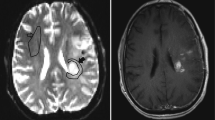

The two readers in this study were a board-certified radiologist (AH) and a radiology resident (FS) with 10 and 6 years of experience in neuroimaging analysis, respectively. Both readers were blinded to patient information, and each reader segmented four contralateral NAWM ROIs using ITK-SNAP software (http://www.itksnap.org/) [35] that avoided cortex, large vessels, and ventricles with the following names and instructions (see supplementary information for full reader instructions): (1) CSOp, a planar ROI of 400–450 mm2 drawn on a single slice in the contralateral centrum semiovale approximately 3 mm (~3 slices) superior to the lateral ventricles similar to Conte et al. [9] (Fig. 1A); (2) CSOs: 3 intra-slice 3D spheres of 5 mm diameter (~5 slices) spanning anteriorly to posteriorly in the contralateral centrum semiovale approximately 3 mm superior to the lateral ventricles as done in prior studies [11, 18] and similar to Smits et al. [10] (Fig. 1B); (3) TUMp: a planar ROI of 400–450 mm2 drawn on a single slice in the slice of the center of the tumor as similarly suggested by the Quantitative Imaging Biomarkers Alliance’s (QIBA’s) Stage 2 Consensus Profile guidelines for nrCBV [3] (Fig. 1C); and (4) TUMs: 3 intra-slice 3D spheres of 5 mm diameter (~5 slices) spanning anteriorly to posteriorly in the slice of the center of the tumor (Fig. 1D). If a contiguous single-slice planar ROI was unable to be created, readers were allowed to create 2 planar ROIs on 2 consecutive slices (Fig. 1C). One month later, the patient order was randomized, and each reader repeated NAWM ROI segmentations and recorded the time needed to segment each ROI. nrCBV and nADC maps were calculated by dividing the rCBV and ADC maps by the mean rCBV and ADC values of the NAWM ROIs. A volume of interest (VOI) was segmented on the FLAIR hyperintense tumor using an in-house, semi-automated thresholding method using the Analysis of Functional NeuroImages (AFNI) software (NIMH Scientific and Statistical Computing Core; Bethesda, MD, USA; https://afni.nimh.nih.gov) [36]. Median nrCBV and nADC values of the FLAIR hyperintense tumor were derived using each of the 4 normalization techniques.

Example NAWM segmentations from both readers. NAWM segmentations using A the planar method in the centrum semiovale (CSOp), B spherical method in the centrum semiovale (CSOs), C planar method in the slice contralateral to the center of tumor (TUMp), and D spherical method in the slice contralateral to the center of tumor (TUMs) on T2/FLAIR images and rCBV and ADC maps. NAWM, normal-appearing white matter; rCBV, relative cerebral blood volume; ADC, apparent diffusion coefficient

All four normalization methods in the present study had similar intra-reader repeatability and inter-reader reproducibility as well as IDH-mutation status predictive performance, but there were significant reductions in time when performing the CSO methods compared to the TUM methods. One likely explanation for the increased time to create NAWM ROIs in TUM regions was for cases where the tumor was located in regions with minimal contralateral white matter, such as near subcortical structures or in the temporal lobes (Fig. 1C and D), so delineating a NAWM ROI that avoids gray matter, normal vessels, and ventricles was particularly challenging. Moreover, selecting a NAWM ROI in the tumor slice of those regions would be even more challenging if there was bilateral tumor infiltration. As a result, the present findings may support the usage of the centrum semiovale [8,9,10,11, 18] as a target NAWM region instead of the white matter directly opposite the tumor [3, 4, 17] because the centrum semiovale is reliably a large region of white matter that is easily identifiable to neuroradiologists and research lab members alike, as also similarly stated by Thust et al. [19]. Of note, the current guidelines provided by QIBA’s Stage 2 Consensus Profile for nrCBV propose a > 2 × 2 cm TUMp NAWM ROI [3]. The present results of a similar 400–450 mm2 TUMp ROI—which the study authors proposed given the difficulty of creating a 2 cm ROI in certain tumor regions described above—suggest that although tumor-slice ROIs provide similar diagnostic performance, intra-reader repeatability, and inter-reader reproducibility compared to CSO ROIs, CSO NAWM methods may be better options in terms of time efficiency and ease.